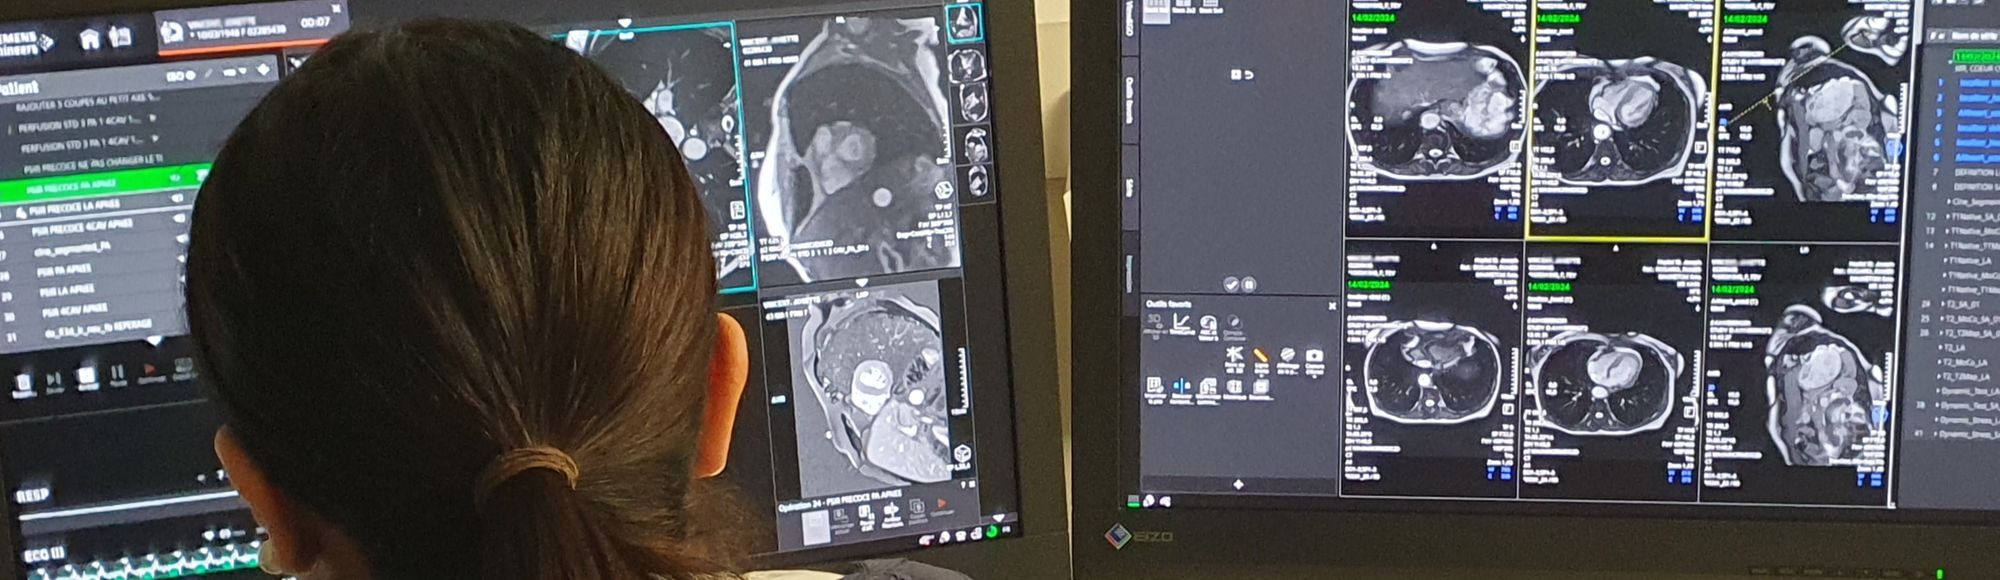

Le service Imagerie Médicale de l'Hôpital vous accueille au sein d'un nouveau bâtiment, Porte B du Bâtiment Buès, où est regroupé le pôle Scanner-IRM. Le Centre de la Femme, au rez-de-chaussée du Bâtiment Fouque, accueille l'imagerie dédiée à la femme (mammographie, échographie mammaire), alors que la radiologie, EOS, et les échographies sont réalisées au 1er étage du Bâtiment De Vernejoul.